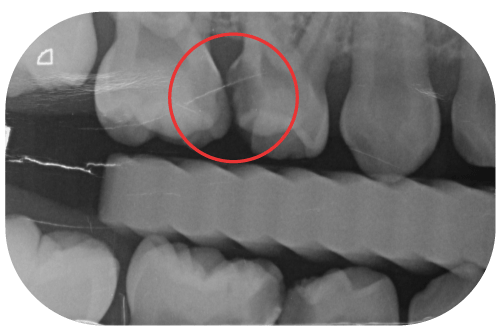

乳臼齒蛀牙已經非常靠近或已經碰到牙髓神經了

當蛀牙範圍已延伸到牙髓神經附近,此時小朋友常伴隨疼痛的症狀,必須先評估該顆牙剩餘齒質多寡、是否足夠支撐日後咀嚼功能?

如果可以,則進行牙髓切除術(俗稱的「抽神經」、「根管治療」)並搭配不鏽鋼牙套。

若牙齒剩餘結構已寥寥無幾,則牙醫師可能會考慮將其拔除,並搭配空間維持器(空間重獲器),以防止乳牙拔掉後的空間被其他牙齒佔據,導致日後恆牙無法順利萌發,造成齒列擁擠或阻生齒等後續衍伸問題。